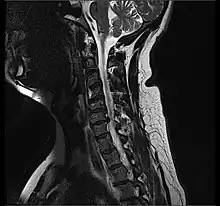

- Magnetic resonance imaging is the gold standard study for confirming a suspected LDH. With a diagnostic accuracy of 97%, it is the most sensitive study to visualize a herniated disc due to its significant ability in soft tissue visualization. MRI also has higher inter-observer reliability than other imaging modalities. It suggests disc herniation when it shows an increased T2-weighted signal at the posterior 10% of the disc. Degenerative disc diseases have shown a correlation with Modic type 1 changes. When evaluating for postoperative lumbar radiculopathies, the recommendation is that the MRI is performed with contrast unless otherwise contraindicated. MRI is more effective than CT in distinguishing inflammatory, malignant, or inflammatory etiologies of LDH. It is indicated relatively early in the course of evaluation (<8 weeks) when the patient presents with relative indications like significant pain, neurological motor deficits, and cauda equina syndrome. Diffusion tensor imaging is a type of MRI sequence used for detecting microstructural changes in the nerve root. It may be beneficial in understanding the changes that occur after herniated lumbar disc compresses a nerve root, and might help in differentiating the patients that need surgical intervention. In patients with a high suspicion of radiculopathy due to lumbar disc herniation, yet the MRI is equivocal or negative, nerve conduction studies are indicated.[43] T2-weighted images allow for clear visualization of protruded disc material in the spinal canal.

MRI scan of cervical disc herniation between C5 and C6 vertebrae. -

MRI scan of cervical disc herniation between C6 and C7 vertebrae -